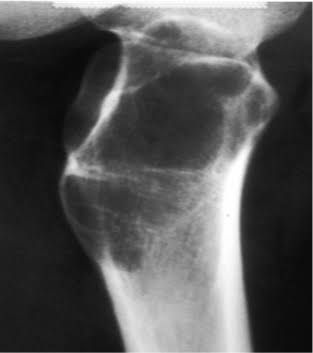

An aneurysmal bone cyst is a benign, blood-filled lesion in the bone that tends to expand or grow. While it is referred to as a cyst, it is a true benign bone tumor surrounded by a thin wall of bone. Aneurysmal bone cysts (ABCs) can occur in any bone, but are most commonly found around the knee, pelvis or spine.